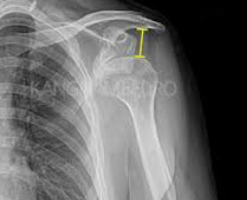

어깨탈구는 어깨 관절이 정상적인 위치에서 벗어나는 상태를 말합니다. 이는 다양한 원인으로 발생할 수 있으며, 통증과 함께 어깨의 움직임이 제한될 수 있습니다. 어깨탈구의 주요 증상으로는 다음과 같은 것들이 있습니다:

1. 갑작스러운 심한 통증: 탈구가 발생하면 어깨 주변의 신경이 자극되어 강한 통증을 느낄 수 있습니다.

2. 어깨의 변형: 탈구된 어깨는 비정상적인 모양을 보이거나 팔이 정상적인 위치에 있지 않게 됩니다.

3. 움직임의 제한: 탈구된 관절은 움직임이 제한되며, 때로는 팔을 전혀 움직일 수 없게 됩니다.

4. 부기 및 멍: 탈구 부위에 혈관이 손상되어 부기나 멍이 생길 수 있습니다.

5. 근육 경련: 탈구된 관절 주변의 근육이 경련을 일으킬 수 있습니다.

어깨탈구는 의학적 평가와 치료가 필요한 상태입니다. 증상이 나타나면 즉시 의료 전문가의 도움을 받아야 합니다. 자가 치료를 시도하지 말고, 전문가에 의한 적절한 진단과 치료를 받는 것이 중요합니다. 어깨탈구는 적절한 치료를 통해 회복될 수 있으며, 재발 방지를 위한 예방 조치도 필요합니다.